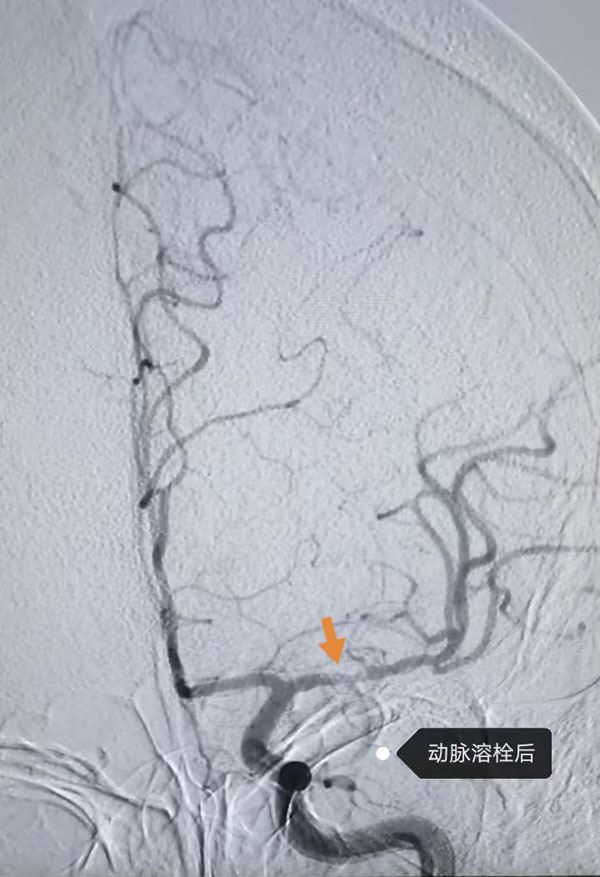

鉴于患者病情危急,接诊医生李晨曦紧急联系介入组李彦青医生启动卒中救治流程,在介入手术室的人员的帮助下,为其实施脑动脉造影术。术中,李彦青发现患者此次发病的责任血管“左侧大脑中动脉”虽存在血流再通,但局部仍为重度狭窄且血栓负荷重,遂决定通过左侧颈内动脉给药以改善局部血供。给药后,复查造影显示狭窄程度明显改善。术后,患者NIHSS评分(神经功能缺损评分)由入院时的8分快速降至3分,言语及右侧肢体活动不利明显改善。一周后出院时,评分进一步降至1分,言语及肢体活动基本恢复正常。

“对于急性缺血性脑卒中患者,血流再通是改善预后的关键。”神经内科主任韩颖表示,“若发病6小时内(静脉溶栓时间窗),优先考虑静脉溶栓;合并颅内大血管闭塞者,经影像评估后24小时内可采取机械取栓、动脉溶栓等血管内治疗,以减轻脑组织损伤、降低致残率。本例患者因属‘醒后卒中',无法通过溶栓治疗,及时的血管内评估与药物干预成为救治核心。”